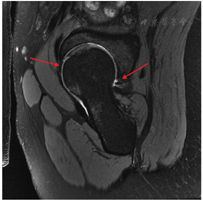

MR影像对FAI患者的术前评估及手术规划尤其重要。MR具有无辐射、多方位、多角度、多参数成像的优点,并且具有较高的软组织分辨力,不仅可观察骨质形态及骨髓的细微变化,还可以观察髋臼盂唇和软骨损伤。正常盂唇在MR影像上应表现为三角形、低信号、边缘光滑的结构,若盂唇的三角形结构形态不规则或出现高信号,提示盂唇损伤。MR可作为早期FAI病变的检查方法,是目前诊断盂唇损伤的基础。MRA通常比普通MRI更准确地评估盂唇和关节软骨病变,但因其有创性,临床上常被3.0 T MRI所替代,因此MRA只用于临床高度怀疑FAI但3.0 T MRI结果正常的患者[67]。

值得注意的是,单髋MRI较双髋MRI分辨率更高,便于观察盂唇结构,临床中更推荐摄单髋MRI片(图6)。读片时应注意髋关节各部分结构的位置,若采取髋臼定位法则以髋臼横韧带的中点是6点钟方向、前方为3点钟方向、上方为12点方向、后方为9点方向。MRI图像中的斜矢状位主要观察前盂唇和后盂唇,该位置是观察盂唇损伤最主要的位置,即1点到4点和11点到7点钟方向;冠状位主要用于观察外上盂唇,即9点到2点方向。

在MRI图像中可直接观察到FAI所致的软骨和盂唇损伤。盂唇损伤在MRA图像中常用Czerny等[68]于1996年提出的分型,将盂唇损伤分为三期:Ⅰ期盂唇损伤图像表示为盂唇内高信号未到达关节面或关节囊面;Ⅱ期盂唇损伤时,盂唇内的高信号到达关节面;而Ⅲ期盂唇的损伤表现为盂唇与髋臼缘的分离。2021年的一项研究将盂唇损伤分为盂唇变性、盂唇-软骨分离、盂唇骨化、盂唇撕裂等类型[69]。而关于髋关节软骨损伤,该研究将软骨损伤分为三个等级[69]:Ⅰ级,正常软骨;Ⅱ级,除软骨全层丢失之外的任何软骨损伤;Ⅲ级,全层软骨丢失。